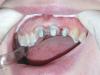

y_veselchak Опубликовано 24 октября, 2008 Поделиться Опубликовано 24 октября, 2008 Думаю, что доктору не нравится тот факт, что у всех трех культей есть явное погружение истонченного края под десну и этот факт не был должным образом учтен. Потому возможно микроподтекание, сложная фиксация и невозможность создания адекватного ферула и уступа. Но что касается трех лет, то я бы не был столь категоричен. Срок службы работы зависит от такого большого количества факторов, что по одной фотографии так сразу предсказать его нереально.Я с большим удовольствием в свое время посетил Вашу лекцию по ВКВ, почерпнул массу интересого и стараюсь. Принимая во внимение исходную картину, вот что получилось во рту - критикуйте Ссылка на комментарий